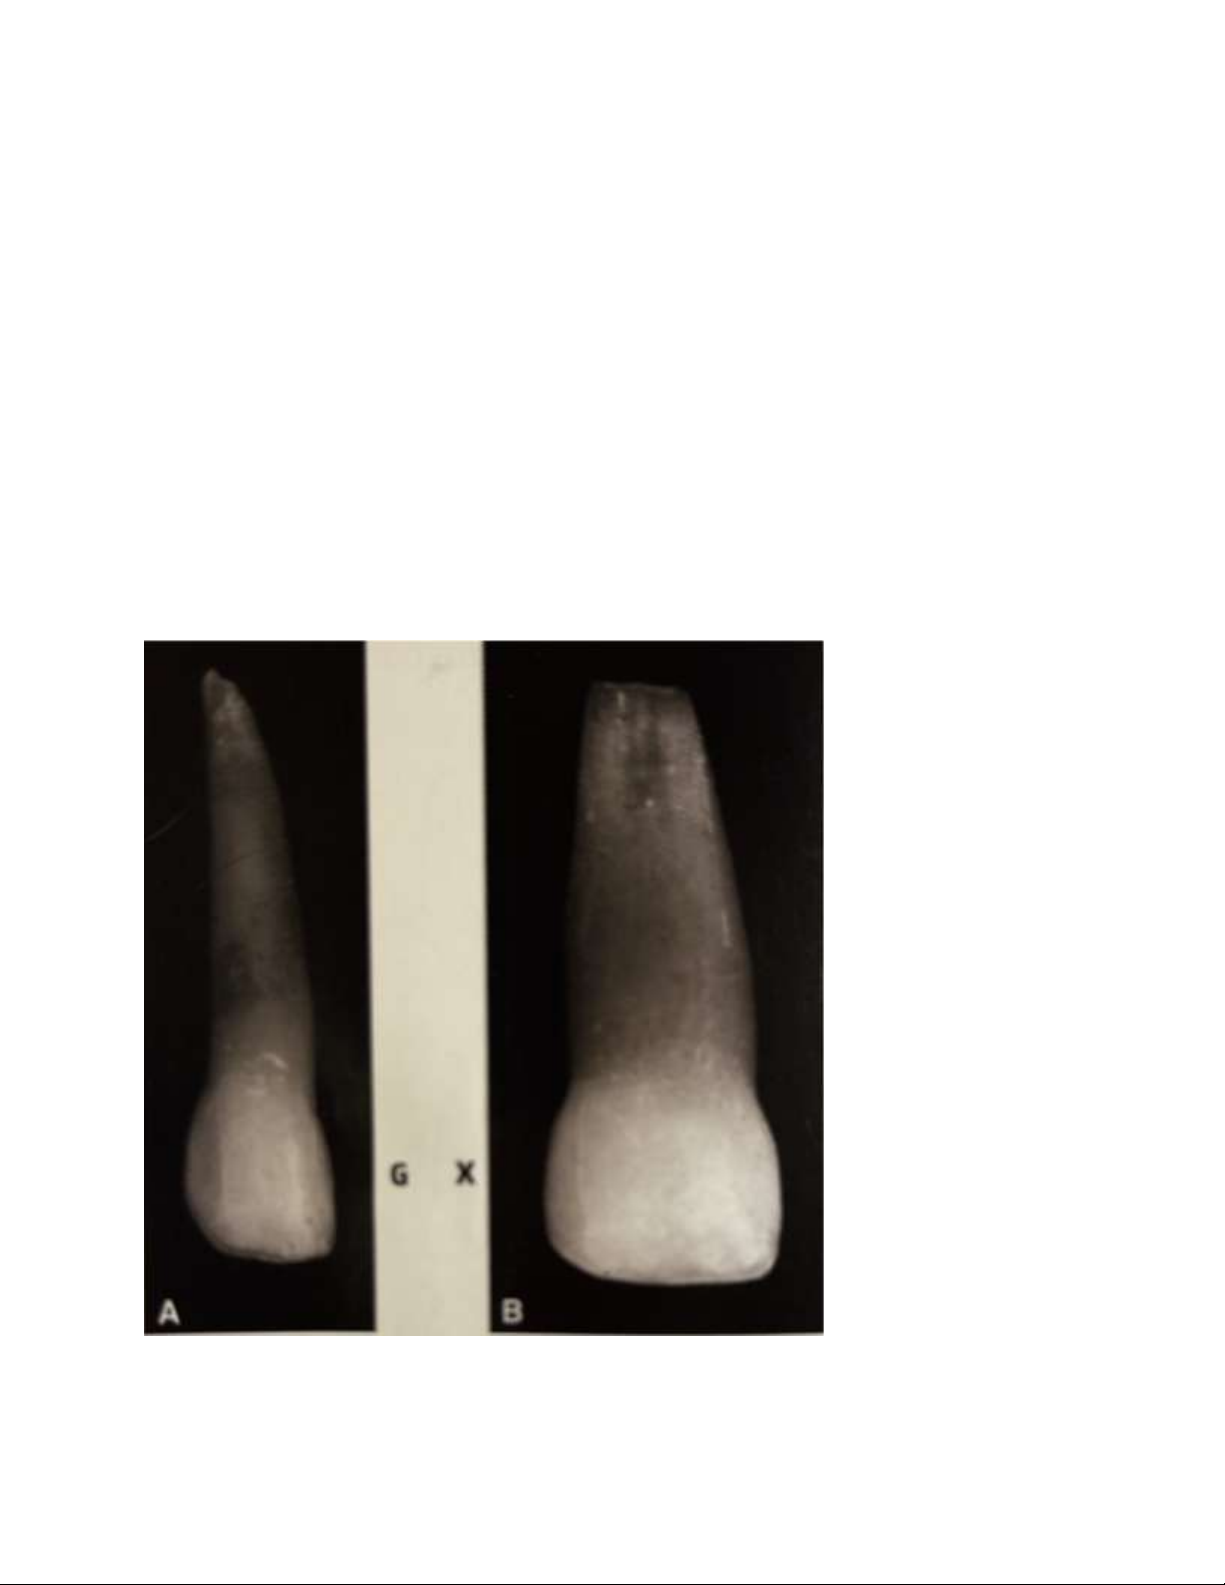

Hình 3. So sánh răng cửa giữa sữa với răng cửa giữa vĩnh viễn: chân răng dài so

với 2 răng và cingulum chiếm hơn nửa mặt trong.

Hình 4. Răng cửa bên (A) và răng của giữa sữa (B). Răng cửa bên có chân rất dài

so với thân răng . Thân răng cửa giữa có chiều ngang lớn hơn chiều cao. lOMoAR cPSD| 59561451

Hình 5. So sánh mặt ngoài răng cửa sữa và vĩnh viễn; kích thước gần xa lớn hơn kích thước nhai nước.